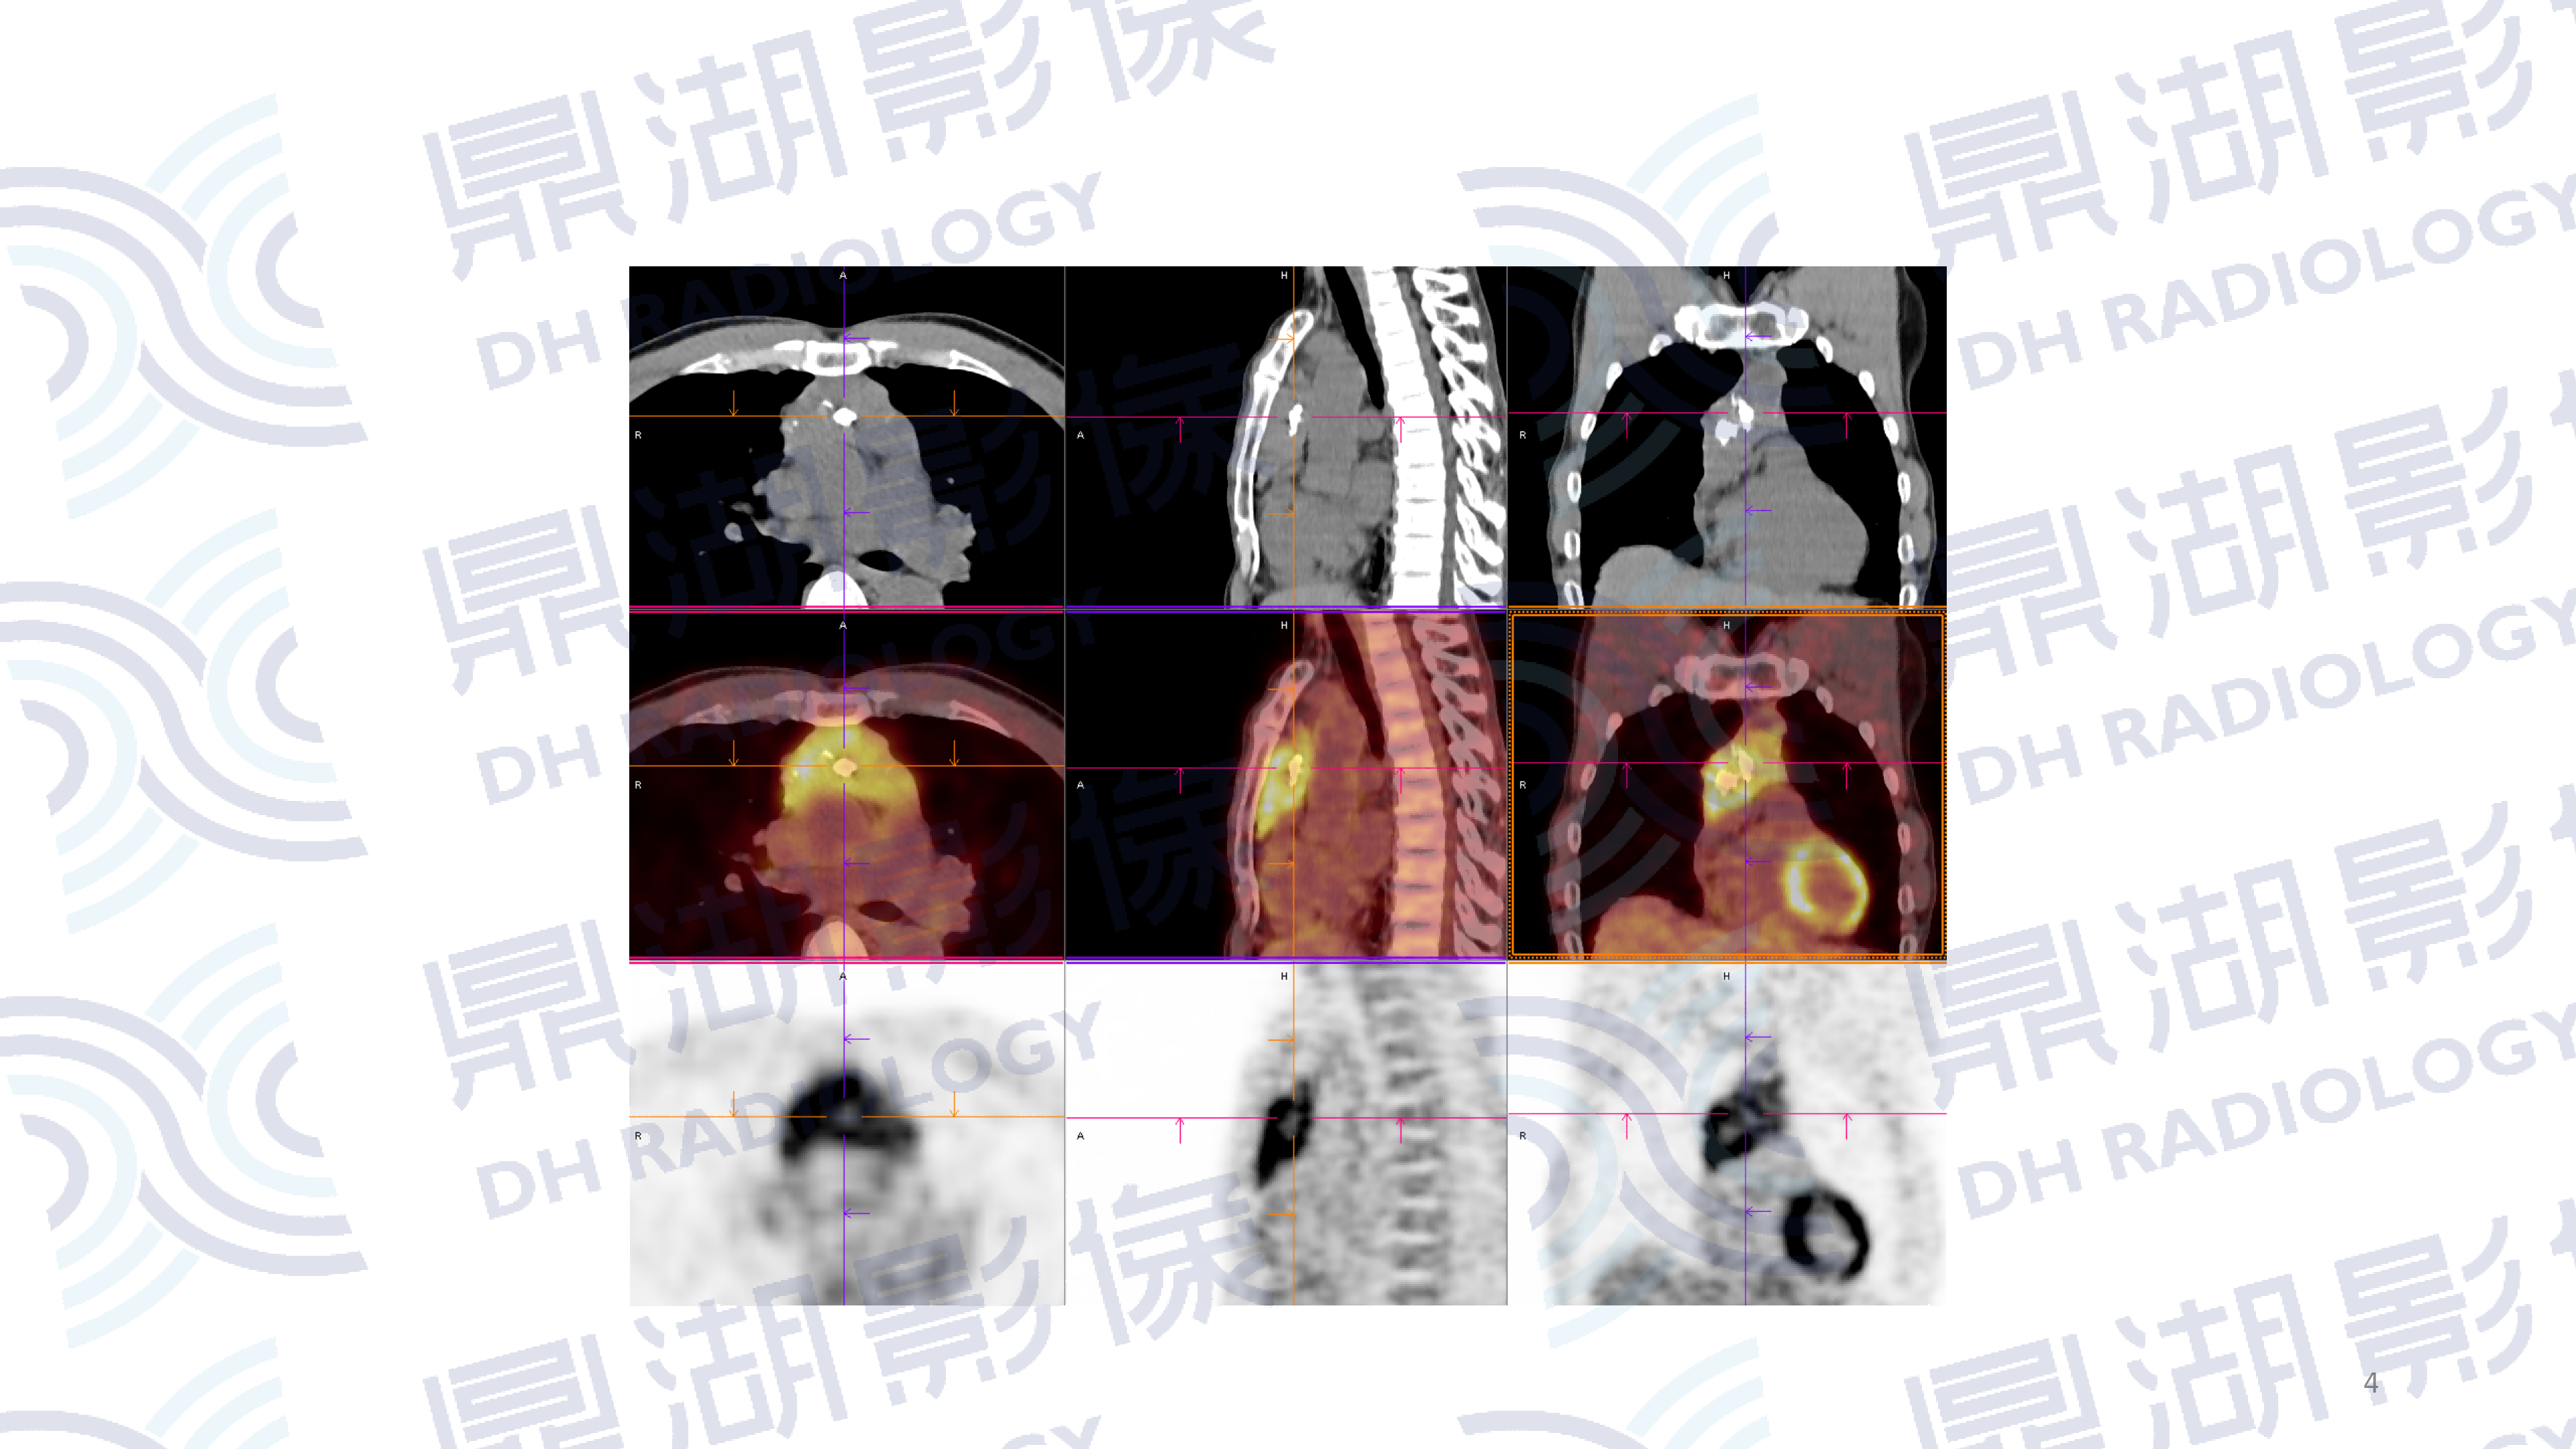

患者,女性,80岁

主诉:左侧肢体无力2周

现病史:患者两周前发现无明显诱因左侧肢体无力、行走不稳伴发热,表现为走路向左侧偏斜,无恶心呕吐,一直未予以治疗。

既往史:无高血压、糖尿病病史;无传染病病史

查体:无明显异常